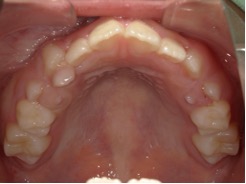

| 年齢・性別 | 8歳3ヶ月の男児 |

|---|---|

| 主訴 | 上顎前歯の位置異常に不安を抱え、歯並びと将来的な咬合状態を整える目的で来院された患者様です。 特に左側の前歯(中切歯および側切歯)の萌出が確認できないことがきっかけとなりました。 |

| 治療期間・回数 | 約5年10ヶ月 |

| 費用 | 460,000円(税別) |